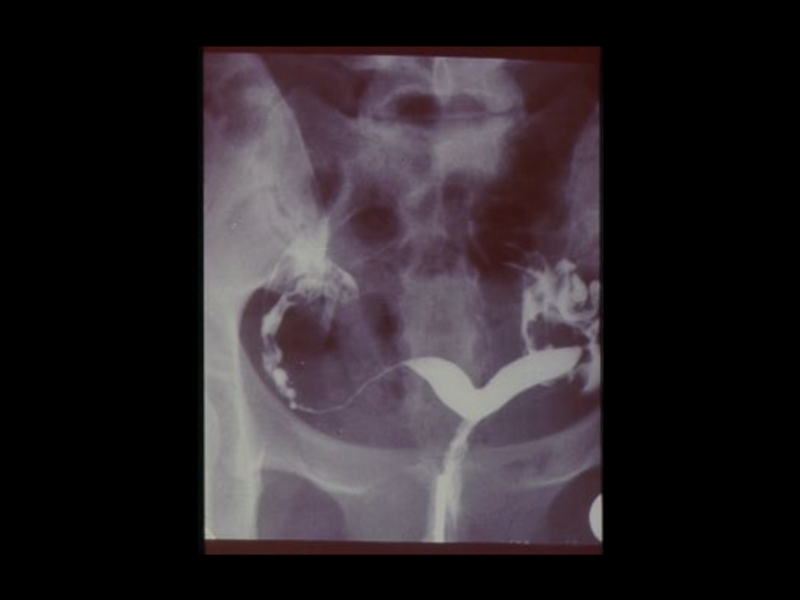

3. Специальные методы

(урография, бронхография, ангиография,

лимфография, пневмоартрография и другие)

Методы традиционной рентгенодиагностики:1. Общие методы   (рентгеноскопия, рентгенография)2. Частные методы   (флюорография, томография,

Слайд 38Виды рентгеноконтрастных веществ:

I. Негативные - газы

( Воздух,

кислород, углекислый газ, закись азота )

II. Позитивные- соли тяжелых металлов

( Сернокислый барий, производные йода )

Виды рентгеноконтрастных веществ:I. Негативные - газы   ( Воздух, кислород, углекислый газ, закись азота )II. Позитивные-

Слайд 39Йодсодержащие рентгеноконтрастные вещества:

I. Ионные - трийодзамещенные

1) Водные (

урографин, уротраст, верографин,

йодамид, триомбраст )

2) Масляные ( Йодолипол, майодил, лимфотраст)

Йодсодержащие рентгеноконтрастные вещества:I. Ионные - трийодзамещенные  1) Водные ( урографин, уротраст, верографин,